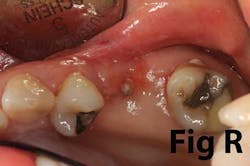

Case No. 1